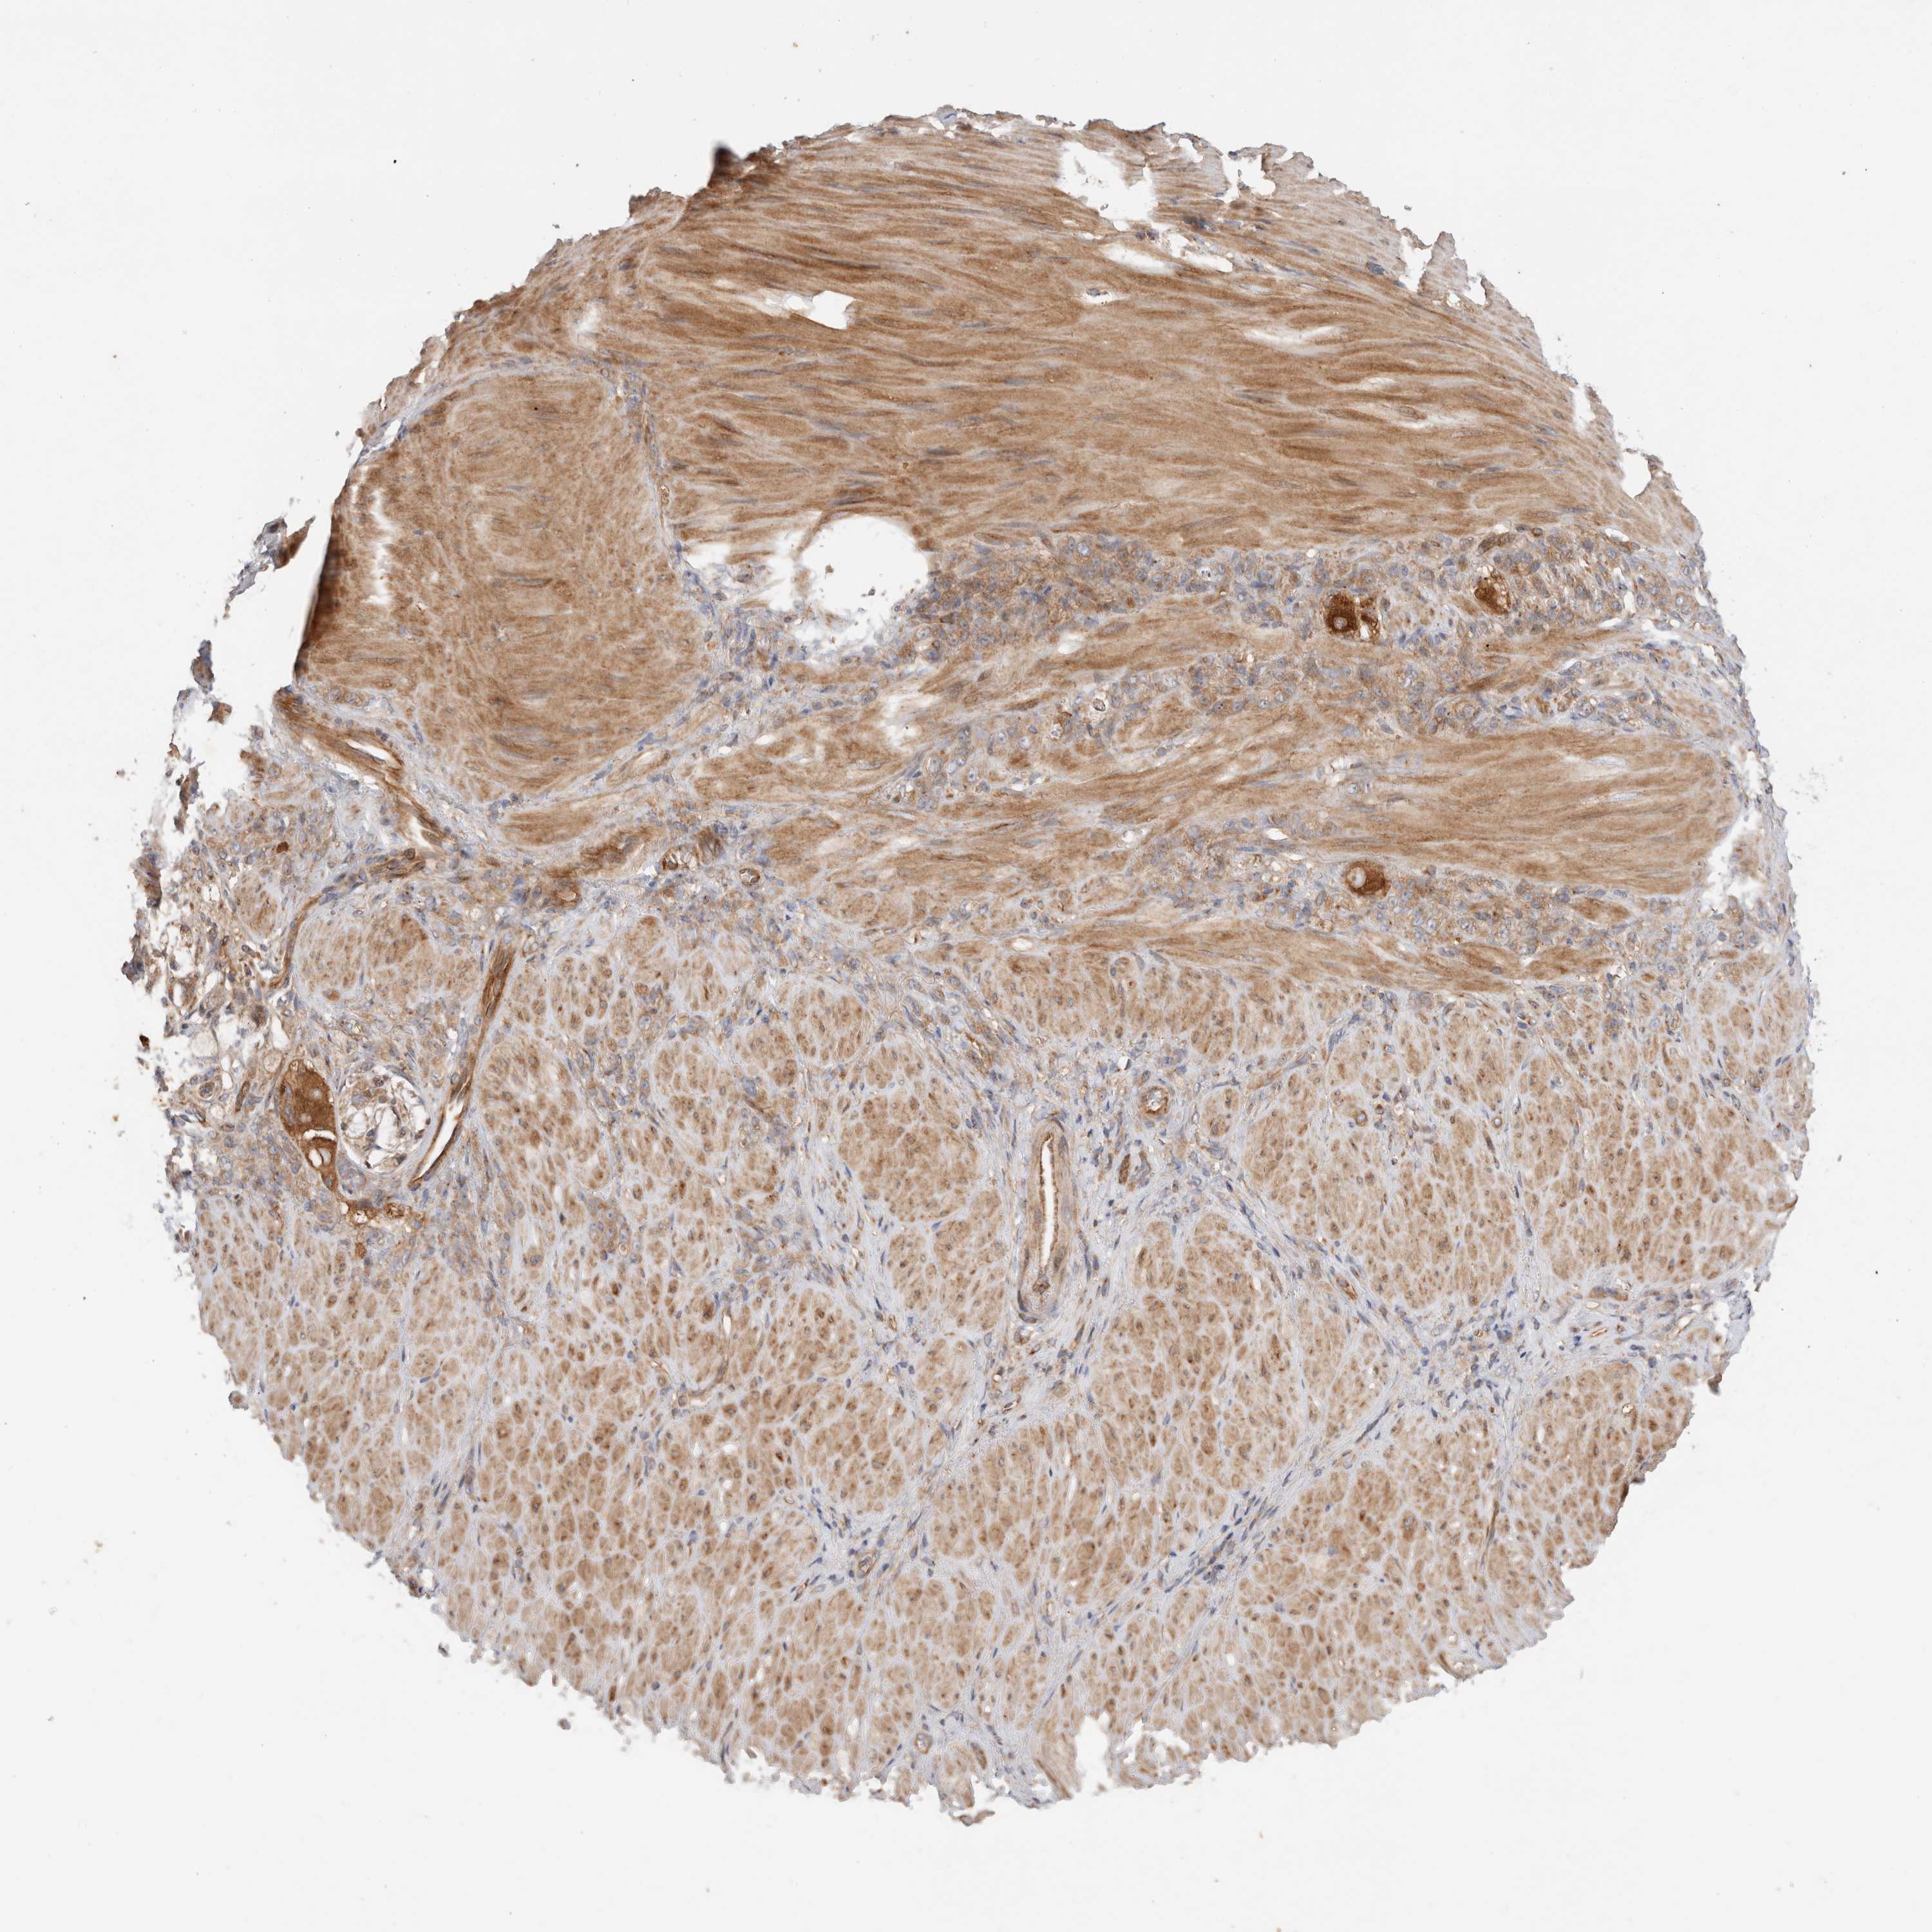

STOMACH CANCER - Protein expressioni

A mouse-over function shows sample information and annotation data. Click on an image to view it in a full screen mode. Samples can be filtered based on level of antibody staining by selecting one or several of the following categories: high, medium, low and not detected. The assay and annotation is described here.

Note that samples used for immunohistochemistry by the Human Protein Atlas do not correspond to samples in the TCGA dataset.

Antibody stainingi

Antibody staining in the annotated cell types in the current human tissue is reported as not detected, low, medium, or high, based on conventional immunohistochemistry profiling in selected tissues. This score is based on the combination of the staining intensity and fraction of stained cells.

Each image is clickable and will lead to virtual microscopy that enables deeper exploration of all samples and also displays staining intensity scores, fraction scores and subcellular localization as well as patient and tissue information for each sample.

Antibody HPA026635

Staining

High

Medium

Low

Not detected

Intensity

Strong

Moderate

Weak

Negative

Quantity

>75%

75%-25%

<25%

None

Location

Nuclear

Cytoplasmic/membranous

Cytoplasmic/membranous,nuclear

Adenocarcinoma, NOS